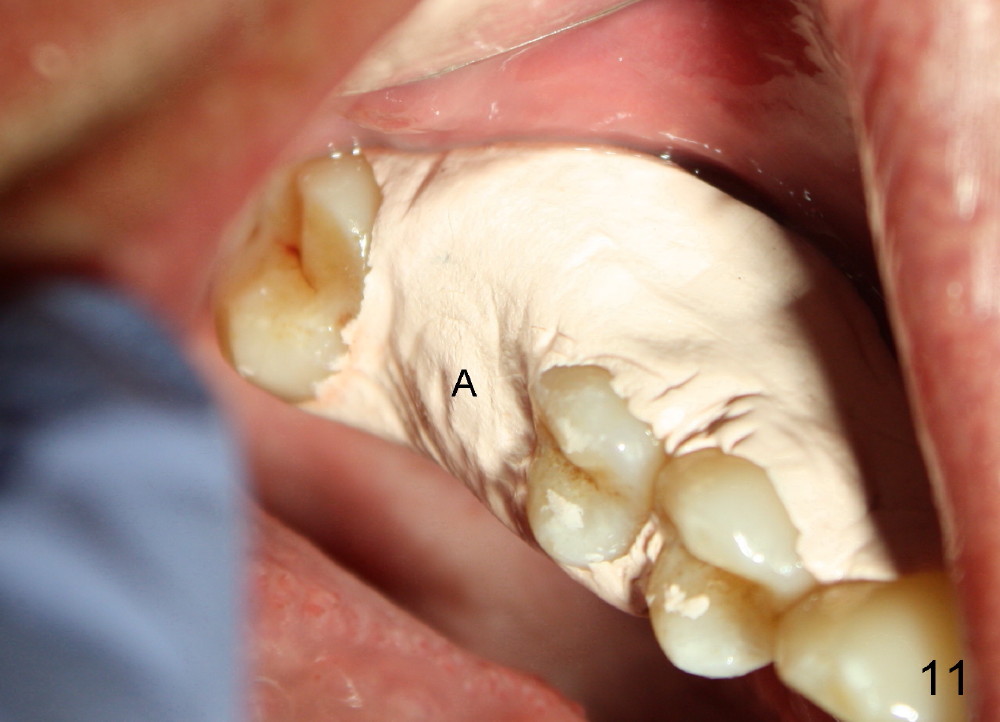

The upper right 1st molar of a 48-year-old man has severe perio endo disease (Fig.1 #3); the bone height for immediate implant (Fig.2) is about 3.5 mm (Fig.1 vertical line). There is a buccal (Fig.3 B) abscess (*); the palatal (Fig.4 P) root is exposed. After extraction, the socket available for immediate implant (Fig.5,6 S) is buccal (without septum), whereas the apex of the palatal root is far away from the main socket. In fact there is an advantage: the socket is smaller. Osteotomy is created in the main socket as palatal as possible, using osteotomes, reamers and taps (Fig.7 T). The sinus floor is lifted (Fig.7 ^). When 7x17 mm implant is placed (Fig.8 I), the insertion torque is >60 Ncm. The remaining socket (Fig.8 *) is to be packed with mixture of autogenous bone, allograft and synthetic bone (Osteogen) (Fig.9,10 <). Immediate insertion of an abutment (Fig.8-10 A) helps retain perio dressing (Fig.11,12). No collagen membrane is used in this case to cover the bone graft before placement of perio dressing. Postop the patient cannot tolerate oral Amoxicillin because of stomach upset. The dose is reduced. Two weeks postop, the perio dressing is stable, but discolors (Fig.13). When the dressing is removed, the buccal bone graft is exposed, which is not abnormal. What is unusual is discoloration (Fig.14). The significance of the latter is not revealed until 3 months postop when the patient remains asymptomatic, but there is an apical fistula (Fig.15 <). There is a communication between the fistula and the buccal sulcus of the implant: water passing freely. Based on the position of the buccal plate of the neighboring teeth (*), the buccal plate of the implant should be lost, which is consistent with finding of PA (Fig.16, as compared to Fig.8). Guided bone regeneration seems necessary.